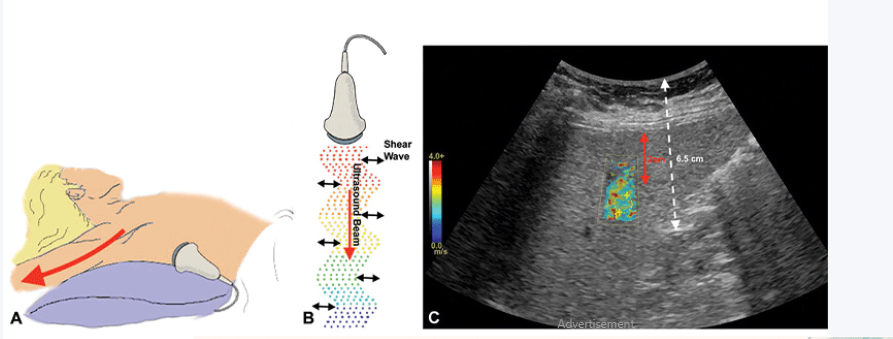

Continue ReadingOverview What is a USG FibroScan of Liver? A USG FibroScan of the Liver (also called Liver Elastography) is a specialized ultrasound test that measures how stiff or elastic your liver is. It helps doctors check for liver fibrosis (scarring) and fatty liver disease — conditions that can develop due to hepatitis, alcohol use, or […]